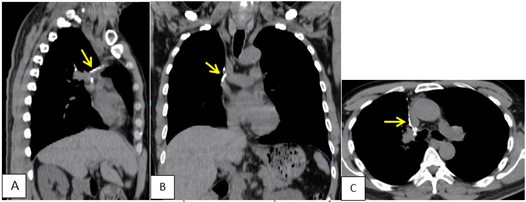

Bệnh nhân đã được theo dõi, khám lại định kỳ. BN đã đuợc chụp CT sau 6 tháng kể từ khi phẫu thuật. Kết quả chi tiết đuợc thể hiện trong hình 5 và 6.

Hình 5. CT ngực BN chụp sau mổ 2 tháng, cửa sổ trung thất trước tiêm cản quang. A: SagitalB: Coronal; C: Axial. A-C: Quan sát thấy các đường may của Stapler khi phẫu thuật cắt thuỳ trên phổi phải (mũi tên)

Hình 6. CT ngực BN chụp sau mổ 2 tháng, cửa sổ nhu mô. A: SagitalB: Coronal; C: Axial. A-C: Phổi phải chỉ còn thuỳ giữa và dưới. Không thấy nốt bất thường nhu mô hai phổi.